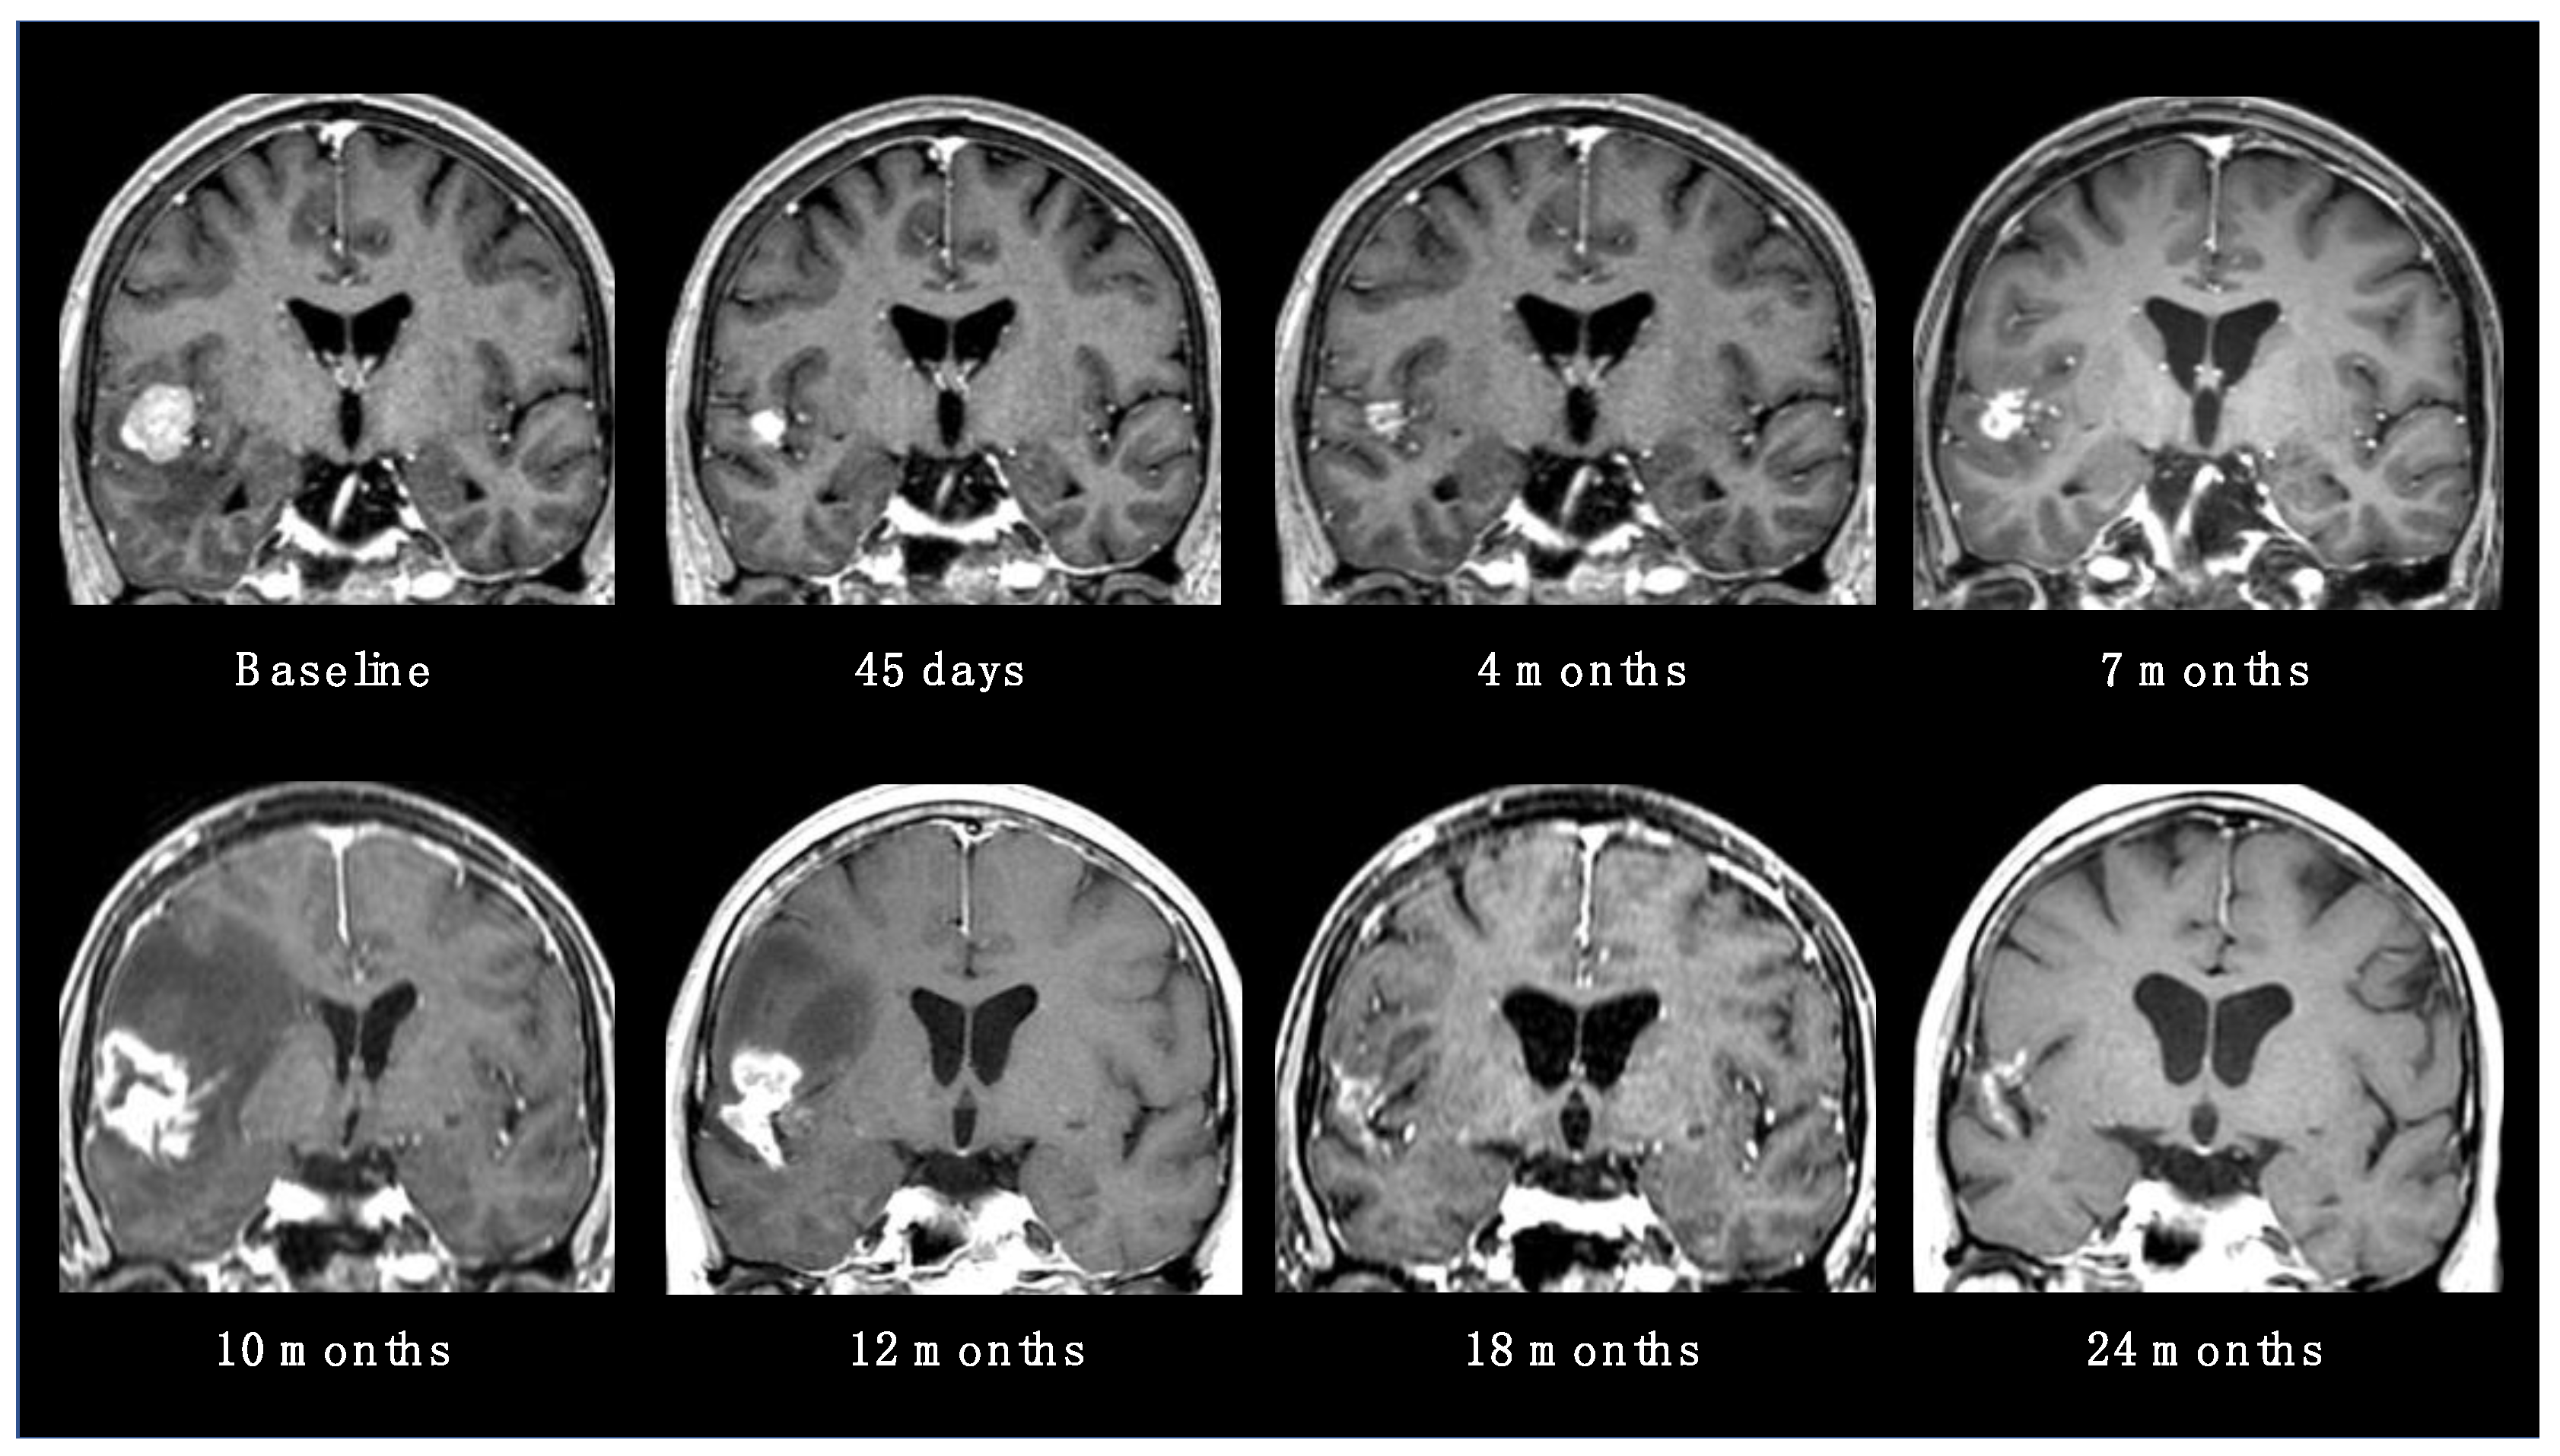

- Walker, A.J.; Ruzevick, J.; Malayeri, A.A.; Rigamonti, D.; Lim, M.; Redmond, K.J.; Kleinberg, L. Postradiation Imaging Changes in the CNS: How Can We Differentiate between Treatment Effect and Disease Progression? Future Oncol. 2014, 10, 1277–1297. [Google Scholar] [CrossRef]

- Vellayappan, B.; Tan, C.L.; Yong, C.; Khor, L.K.; Koh, W.Y.; Yeo, T.T.; Detsky, J.; Lo, S.; Sahgal, A. Diagnosis and Management of Radiation Necrosis in Patients With Brain Metastases. Front. Oncol. 2018, 8, 395. [Google Scholar] [CrossRef] [PubMed]